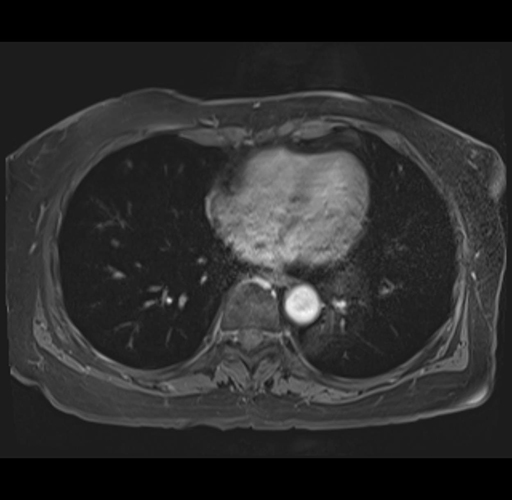

MRI T1

Imaging analysis